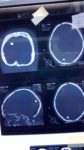

دون أي مضاعفات نجاح عملية إزالة شظية من الجهة اليمنى الخلفية لرأس شاب عمره “21” عام

كللت العملية التي أجراها رئيس قسم جراحة المخ والأعصاب بالمستشفى الجامعي طرابلس الدكتور” فيصل طالب”، والفريق الطبي المرافق له خلال الأيام الماضية بالنجاح التام لشاب يبلغ من العمر 21 عام أصيب بشطية دخلت من الأنف وتوقفت في الجهة اليمنى الخلفية للرأس، وبعد الكشف وإجراء الفحوصات اللازمة قرر الفريق الطبي ضرورة إجراء عملية جراحية بشكل عاجل لإنقاذ حياته وإزالة الشظية>

العملية التي استغرقت أكثر من ساعتين بذل خلالها كل من الأطباء “فيصل طالب” ، “عبد السلام الدعيكى”

، “أسامة قنديل” جهود مضنية لضمان نجاح العملية التي كللت بالنجاح دون أن تسبب له مضاعفات، ووضع المريض تحت الملاحظة الكاملة من قبل الأطباء المناوبين لأكثر من “72” ساعة قبل إحالته للقسم ومتابعته من قبل الأطباء المختصين الذي قرروا منحه إذن خروج بعد تماثله للشفاء على أن يقوم بمراجعة أطباء القسم بشكل دوري.